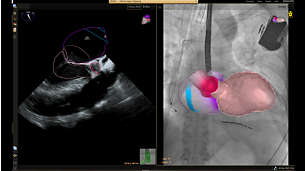

Image Guided Therapy System—Azurion

Azurion provides the ability to treat one more patient per day, reducing procedure time by 17%* with optimized workflow options in interventional therapy and clinical software. *Reducing procedure time by 17%, with the ability to treat 1 more patient per day with optimized workflow options in image guided therapy and clinical software (Azurion - Philips Azurion Simulation Study 2016 - 12NC 452299123041 - FEB 2017). Results are specific to the institution where they were obtained and may not reflect the results achievable at other institutions.